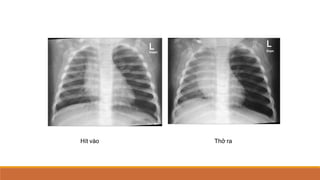

Chụp thì thở ra

Tìm ứ khí ở phổi khu

trú hay lan tỏa

Tràn khí màng phổi

Hít vào Thở ra